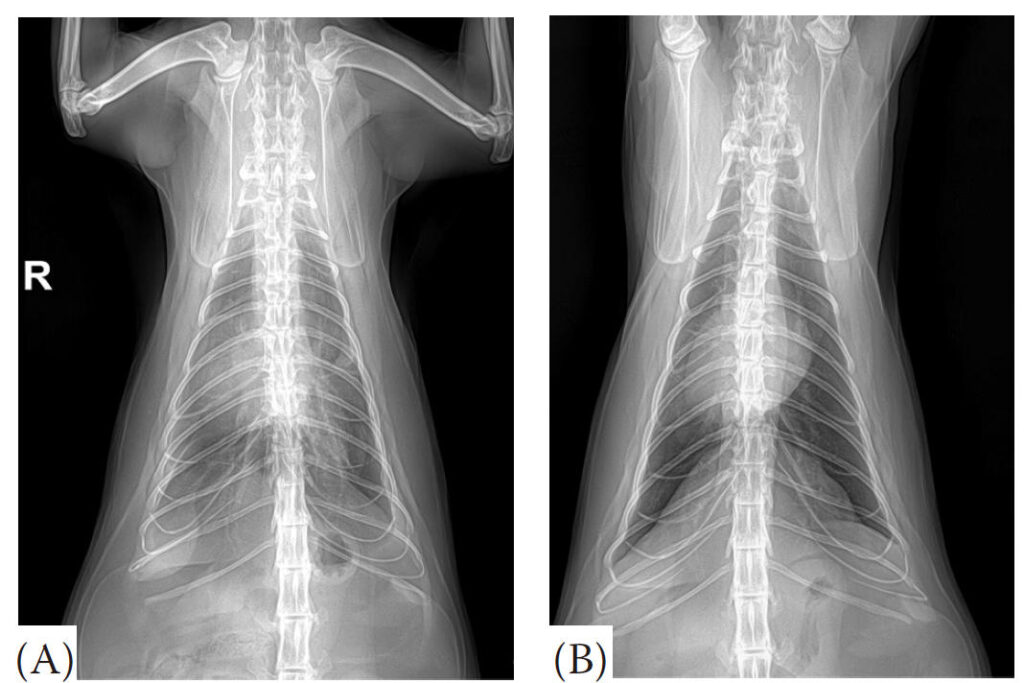

胸部X光显示心脏呈心形增大,椎体心脏大小为8.2 [6.8–7.8]。双侧后肺叶可见肺泡和间质模式,符合肺水肿表现。叶间裂线提示有胸腔积液。

经过2天的治疗,呼吸困难得到缓解,呼吸频率从每分钟60次降至30次。随后的胸部X光显示肺水肿和胸腔积液有显著改善(下图)。

↑ 治疗前(A)和治疗后(B)的胸部腹背位X光片。(A)初始X光片显示肺水肿和胸腔积液。(B)治疗后2天拍摄的随访X光片显示肺水肿和胸腔积液有所改善。

本病例描述了一只12岁的去势雄性短毛猫,因呼吸困难就诊,最终被诊断为伴有左前分支阻滞(LAFB)薄壁及低动力心肌节段(THyMS)的HCM。在临床检查中,该猫表现出呼吸急促、心尖区收缩期杂音和肺部啰音,胸部X光显示心脏呈“心形”增大,伴有肺水肿和胸腔积液。

在治疗方面,该猫接受了氧疗、利尿剂(呋塞米)、正性肌力药物(匹莫苯丹)和抗凝治疗(达肝素),以改善呼吸困难和预防血栓栓塞并发症。经过2天的治疗,呼吸困难得到缓解,胸部X光显示肺水肿和胸腔积液明显改善。